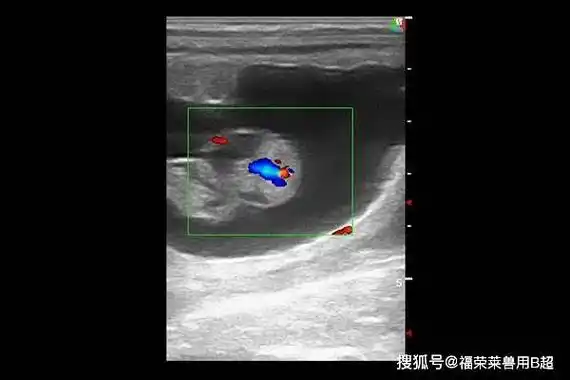

帮你了解母马的解剖学,生理学及繁殖_黄体期_子宫_卵泡